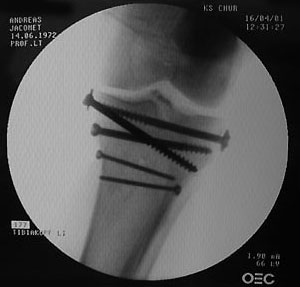

So geht das heutzutage: Kein Gips mehr, dafür vom Anfang an Bewegungsschiene (unter Schmerzen, die ich selbst Monate später noch als Gipfel der Tortur empfand, und das trotz einer geballten Ladung Morphium & Co.).

Belastet werden darf die ganze Konstruktion allerdings nicht, zumindest sechs Wochen lang - Titan und Edelstahl zierten für die nächsten Monate das Schienbein; ans Tageslicht kamen die erstaunlich grossen Schrauben erst im November wieder. Die folgenden Bilder wurden während der Operation gemacht: